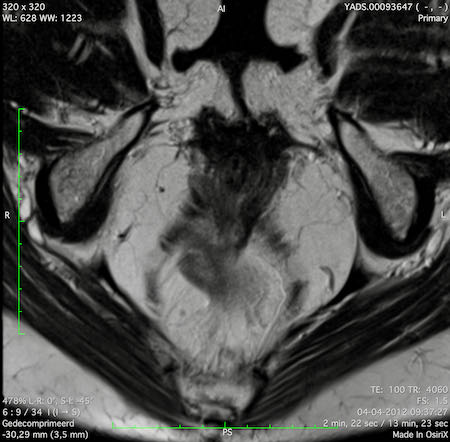

Đặc điểm MRI

- Thường khó xác định

- Thường biểu hiện nhưdày thành ruột lan tỏa, đoạn dài

- Kiểu tăng trưởng dưới niêm mạc, cho ra mộtHình ảnh “bia” (target)trên các hình ảnh cắt ngang

- Thâm nhiễm mỡ trực tràng lan tỏalà phổ biến

Hình ảnh

Các hình ảnh được cung cấp cho thấy ung thư biểu mô tế bào nhẫn với tình trạng dày lan tỏa thành trực tràng, hình ảnh bia bắn điển hình, và sự xâm lấn mỡ mạc treo trực tràng.